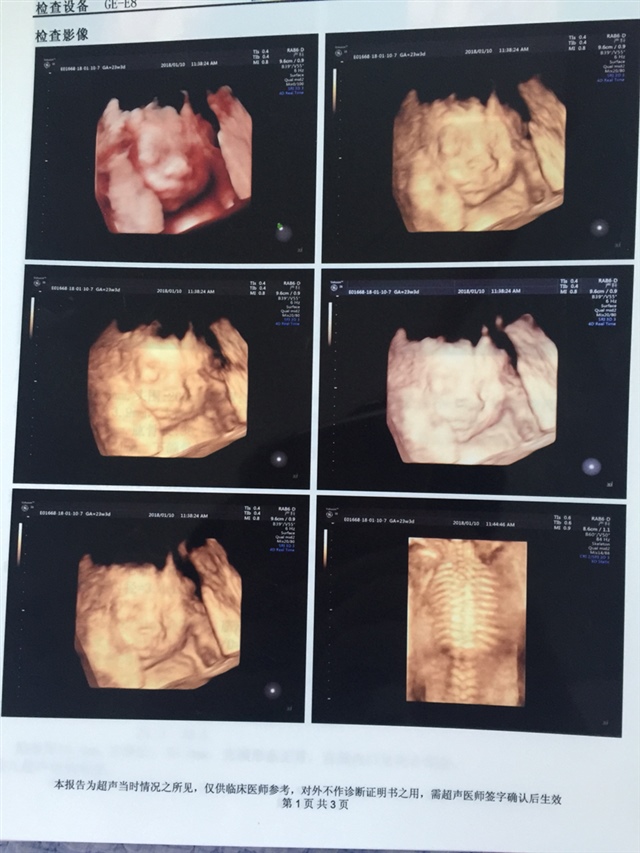

宝宝3个月20天

孕18周+4天

孕14周+6天

孕25周+1天

孕15周+0天